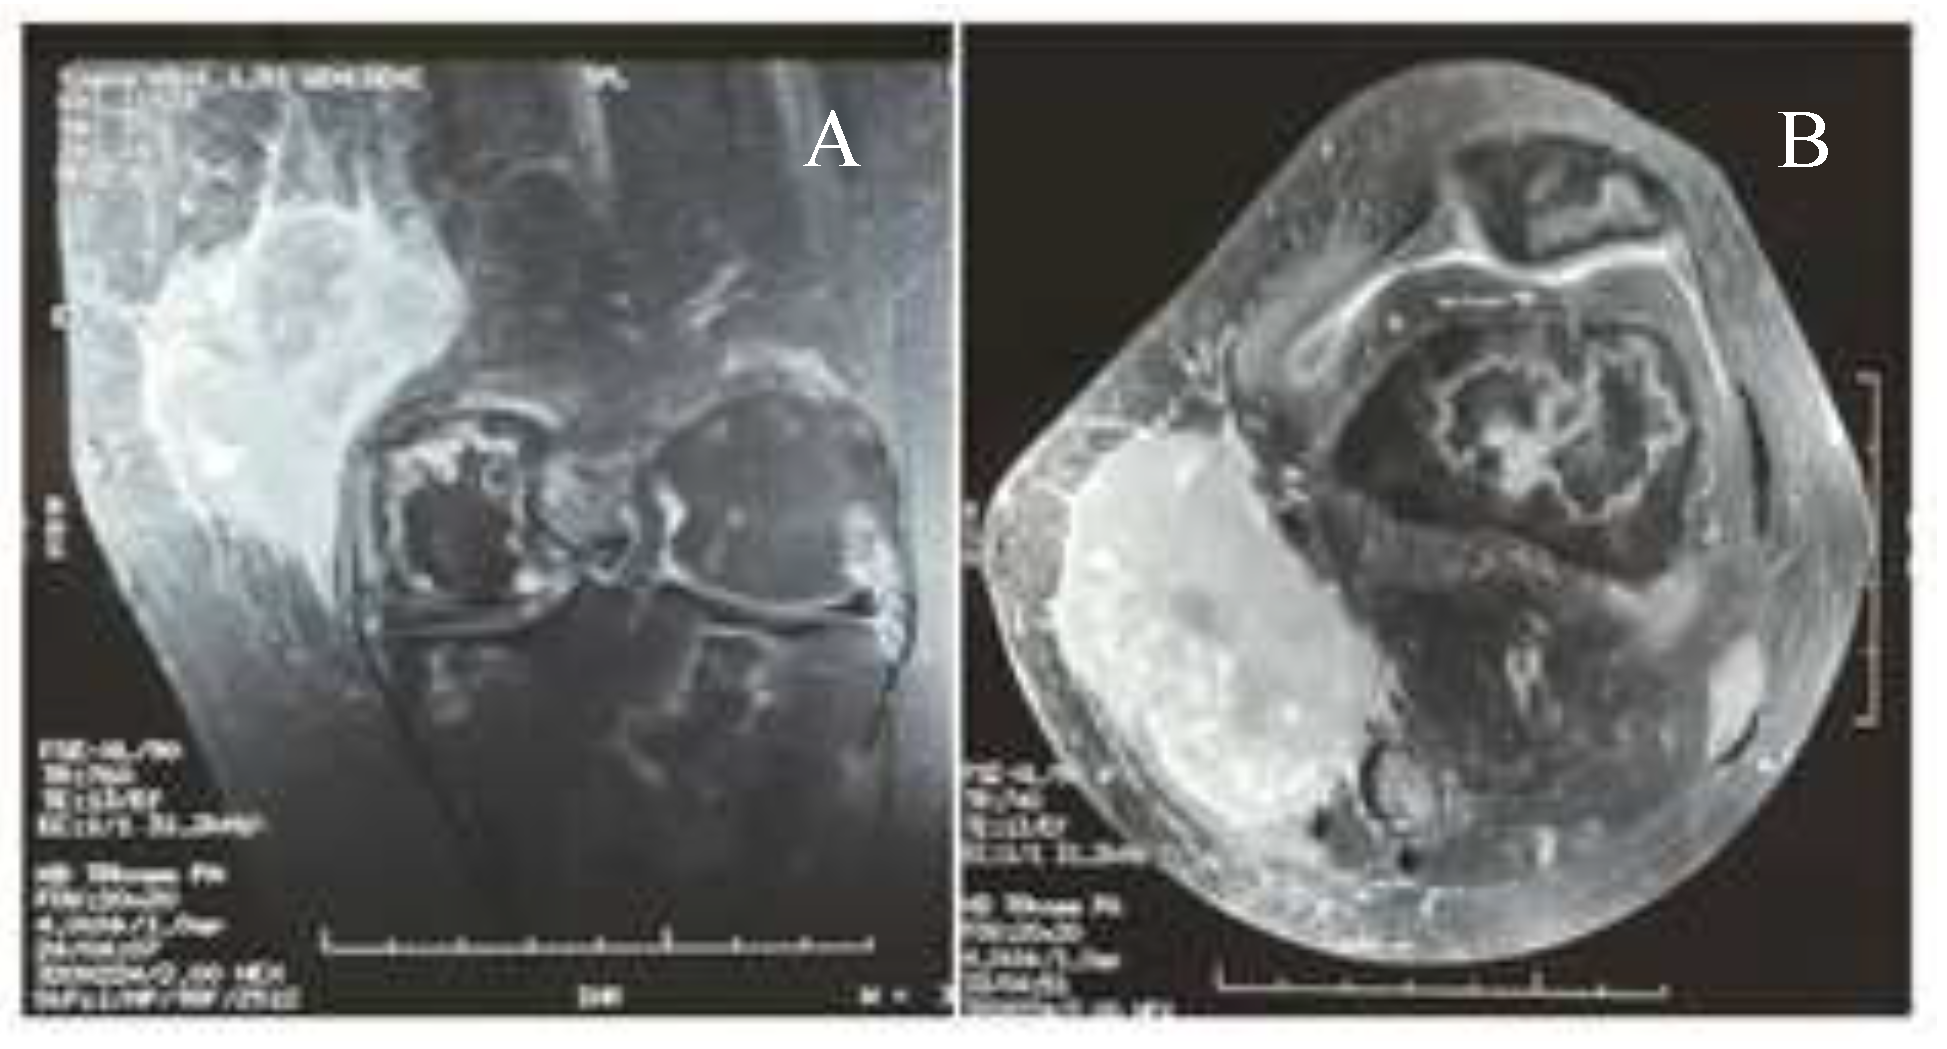

- Nishida, H.; Kinoshita, T.; Yashiro, N.; Ikeda, Y.; O’Uchi, T. MR findings of granulocytic sarcoma of the breasts. Br J Radiol. 2006, 79, e112–e115. [Google Scholar] [CrossRef] [PubMed]